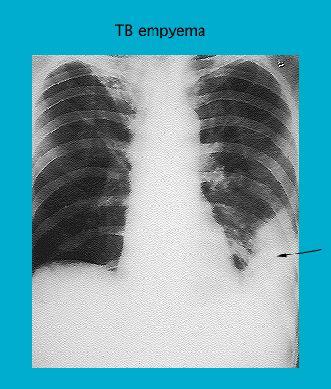

Radiograph showing TB empyema